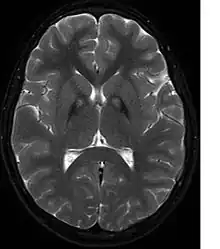

A neurological examination would show evidence of muscle rigidity; weakness; and abnormal postures, movements, and tremors. If other family members are also affected, this may help determine the diagnosis. Genetic tests can confirm an abnormal gene causing the disease. However, this test is not yet widely available. Other movement disorders and diseases must be ruled out. Individuals exhibiting any of the above listed symptoms are often tested using MRI (Magnetic Resonance Imaging) for a number of neuro-related disorders. An MRI usually shows iron deposits in the basal ganglia. Development of diagnostic criteria continues in the hope of further separating PKAN from other forms of neurodegenerative diseases featuring NBIA.

Microscopic features of PKAN include high levels of iron in the globus pallidus and the pars reticulata of substantia nigra, evident as a characteristic rust-brown discoloration[7] in a pattern called the eye-of-the-tiger sign;[8] lipofuscin and neuromelanin concentrated in the iron-accumulating areas; oval, nonnucleated structures representing swollen axons whose cytoplasm swells with vacuoles, referred to as spheroids, axon schollen, or neuroaxonal dystrophy; and Lewy bodies.[7]